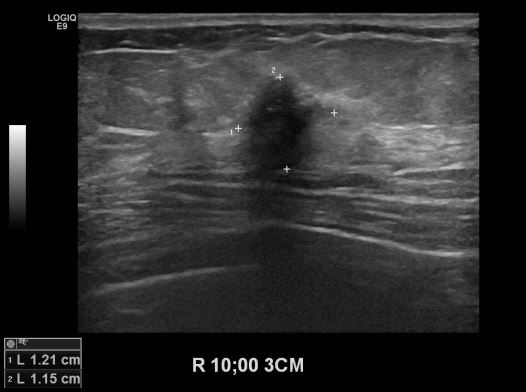

상기환자 유측유방의 멍울로 내원하신 60대 여성분으로 본원 초음파상 우측 10시 방향에서 3 cm 떨어진 거리의 멍울 조직검사 시행하여 우측 침윤성 유관암 진단 되었습니다.